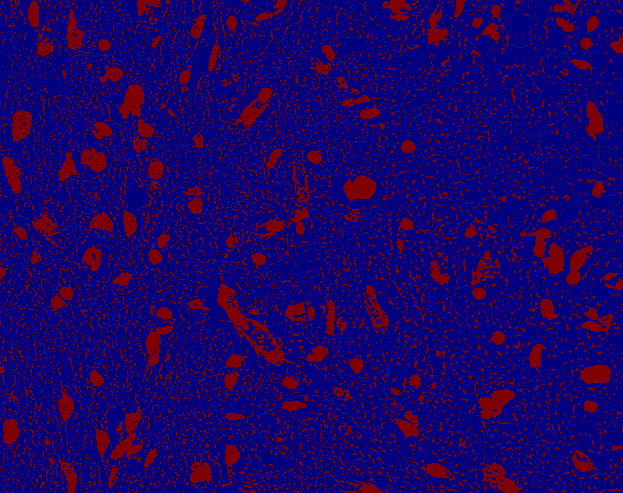

Technical Details

Pipeline

Thresholding

input

color clusters

top 3

most intensive clusters sum

1

6

5

4

3

2

4+5+6

K-means clustering

Parameters:

- number of color clusters

- number of most most intensive clusters to be classified as nuclei

Models

- k-means(3,1)

- k-means(4,2)

- k-means(6,3)